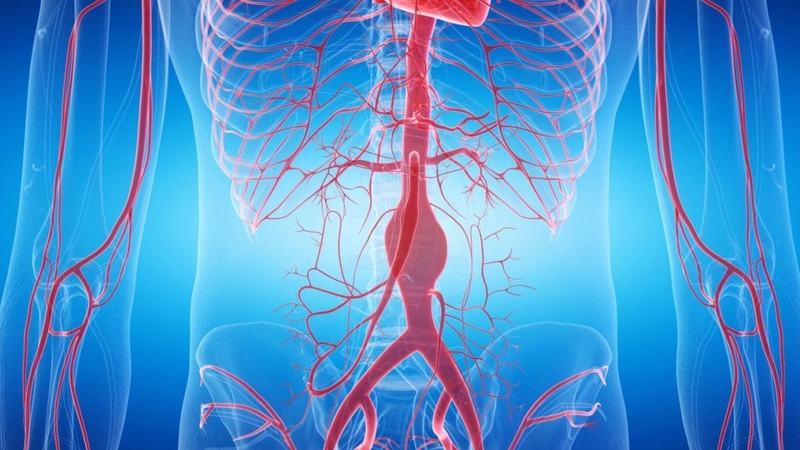

Chụp DSA hay còn được biết đến với tên gọi chụp mạch máu kỹ thuật số hóa xóa nền là một phương pháp chẩn đoán hình ảnh tiên tiến được sử dụng để đánh giá chi tiết các mạch máu trong cơ thể. Phương pháp này sử dụng một loại cản quang đặc biệt được tiêm vào các động mạch, sau đó các bức ảnh chụp X-quang sẽ được thực hiện.

Thông qua kỹ thuật này, các bác sĩ có thể có được hình ảnh chi tiết và rõ ràng về hệ thống mạch máu, giúp phát hiện sớm và chính xác các vấn đề như tắc nghẽn, phình mạch, hay dị dạng động - tĩnh mạch.

Chụp DSA có khả năng cung cấp hình ảnh chất lượng cao với độ phân giải vượt trội, cho phép các bác sĩ thấy được những thay đổi nhỏ nhất trong cấu trúc mạch máu. Điều này đặc biệt quan trọng trong việc chẩn đoán và lên kế hoạch can thiệp cho các bệnh nhân mắc phải các bệnh lý phức tạp ở não, cổ, ngực và các chi.

Ví dụ, trong điều trị bệnh lý mạch máu não như phình động mạch não, DSA giúp xác định chính xác vị trí và kích thước của túi phình, từ đó hỗ trợ các bác sĩ trong việc lựa chọn phương pháp can thiệp phù hợp nhất như đặt stent hay thực hiện nong mạch.